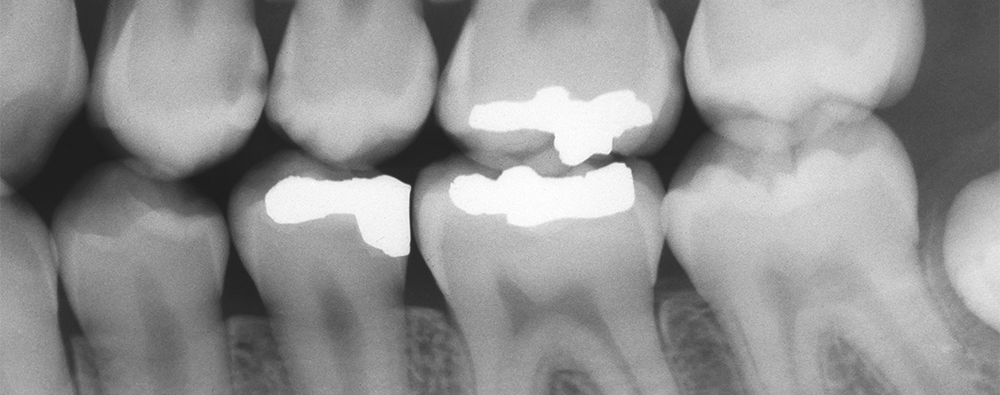

• Cavities and tooth decay – not just for grown-ups: Cavities can sneak up on kids, especially if oral hygiene practices are inconsistent. And tooth decay is one of the most prevalent oral health issues in children. Monitor your child's brushing and flossing routine and promote the use of fluoride toothpaste. Diet goes a long way, too, so limit sugary snacks, too. Sealants, a thin protective coating, can also be applied to the chewing surfaces of molars to prevent cavities.